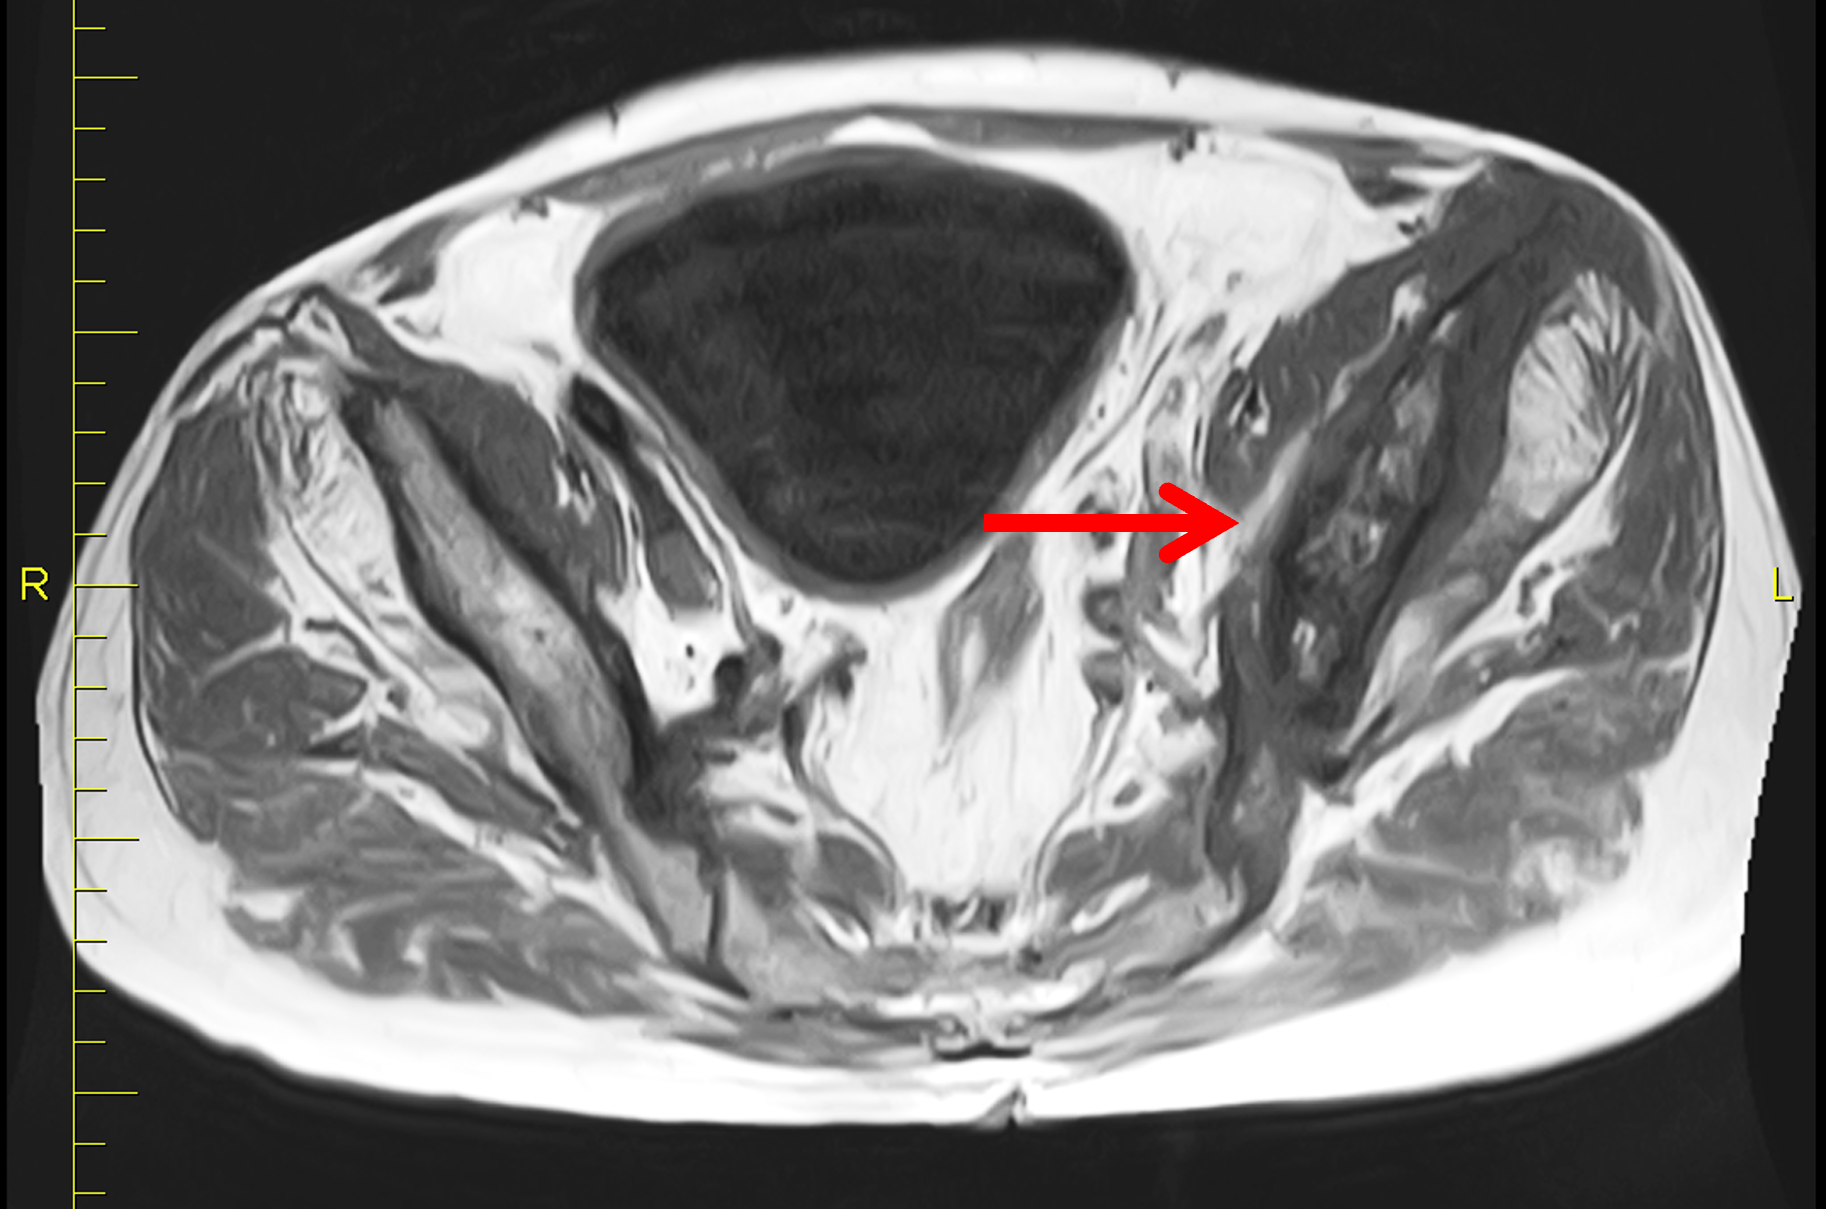

Figure 2: (2A) Sagittal T1-weighted image shows severe thickening of the distal femoral cortex (yellow arrow) and thickening and coarsening of the trabeculae in the femoral condyles (red arrow). Note the high signal intensity fatty marrow in both regions. (2B) Axial fat-suppressed, fluid sensitive sequence through the distal femoral shaft shows severe thickening of the bone cortex, with small round and tubular high-signal intensity foci within the cortex (arrow), likely representing cysts and dilated vascular spaces. (2C) Axial fat-suppressed, fluid sensitive sequence through the femoral epicondyles shows heterogeneous marrow (asterisks), with areas of suppressed marrow fat, mildly increased marrow signal intensity, and small cyst-like lesions. (2D) AP radiograph shows typical findings of mixed phase Paget disease in the distal femur including cortical thickening, course trabeculae, and bone enlargement. Secondary medial compartment predominant osteoarthritis has developed, likely contributing to symptoms.

Figure 6: Lytic to early mixed phase Paget disease of the distal femur. (6A) Lateral radiograph shows extensive osteolysis and coarse trabeculae in the femoral shaft (asterisk). It is often difficult to confidently identify thickened cortex during the active phase of osteolysis. Note the sharp transition from Pagetoid bone to normal bone distally (between arrows). (6B) Axial fat-suppressed, fluid-sensitive image demonstrates mildly thickened cortex containing tubular areas of very high signal intensity (arrows), suggesting dilated vascular channels.